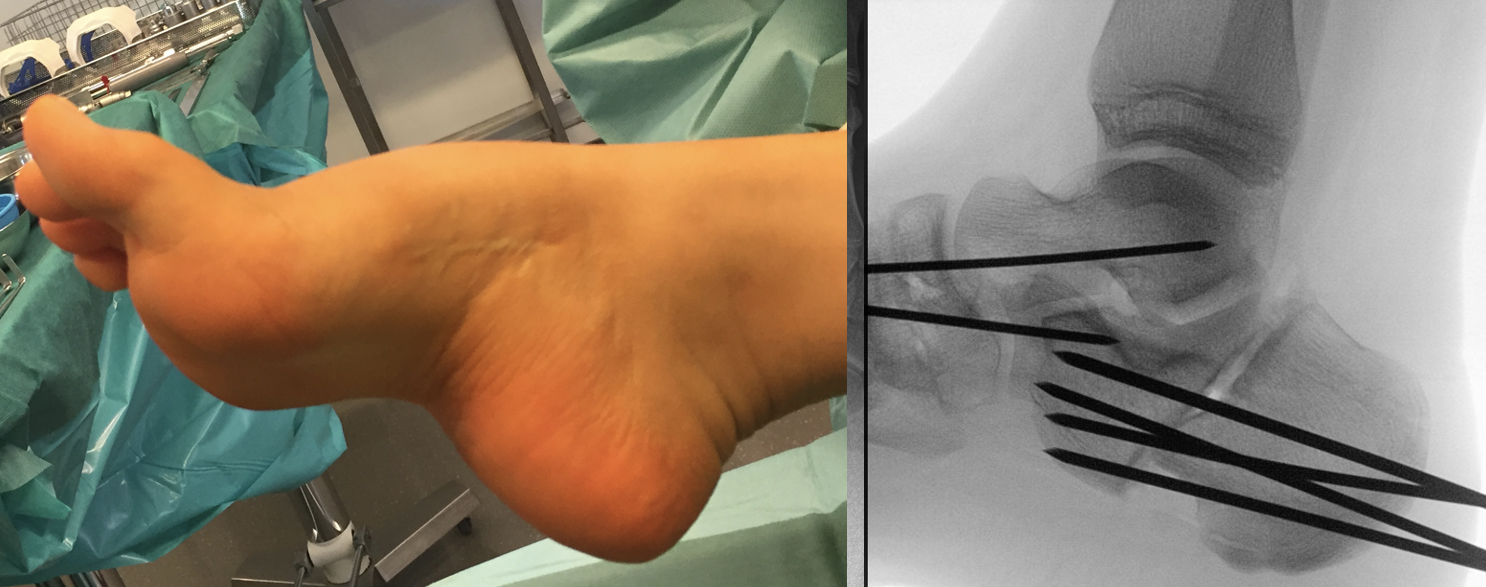

Calcaneus-Osteotomie

Die minimalinvasive Calcaneusverschiebeosteotomie bietet eindeutige Vorteile gegenüber dem offenen Verfahren, sodass wir bei Kindern und Jugendlichen nahezu keine offene Verschiebeosteotomie mehr durchführen. Am Calcaneus liegt die offene Wachstumsfuge dorsal. Bei der Durchführung müssen Schenkel der V-förmigen Osteotomie daher etwas steiler angelegt werden, in einem stumpfen Winkel (siehe Abb. 3 a-j). Für die Osteotomie liegen unsere Patienten auf dem Rücken und der BV wird für die exakte Seitaufnahme eingestellt. Der Fuß lagert auf einem hohen OP-Kissen und die Osteotomie kann bequem mit einem langen Kirschner-Draht und einem sterilen Stift angezeichnet werden (Abb. 15).

Abb. 15 a-b: Lagerung für die Calcaneus-Osteotomie minimalinvasiv.

Damit lässt sich im Verlauf Röntgenstrahlung für die jungen Patienten vermeiden und die minimalinvasive Osteotomie kann sicher durchgeführt werden. Anschließend erfolgt die Verschiebung oder Impaktion. Ist ein Gleiten nach plantar oder cranial des distalen Fragmentes erwünscht, wird die Osteotomie schräg ohne V-Form entweder verlängernd oder verkürzend durchgeführt (Abb. 16).

Durch den knöchernen Defekt der Fräse gelingt die Verschiebung bei der minimalinvasiven Osteotomie im Fall von strukturell festen Klumpfüßen mit starkem Zug der verkürzten Achillessehne oder bei einer fixierenden spastischen Grunderkrankung einfacher gegenüber dem offen Verfahren. Ein weiteres Plus bei hyperaktiven Weichteilen ist die Vermeidung der ungewollten Cranialisierung des dorsalen Fragmentes durch die V-förmige Osteotomie (Abb. 16).